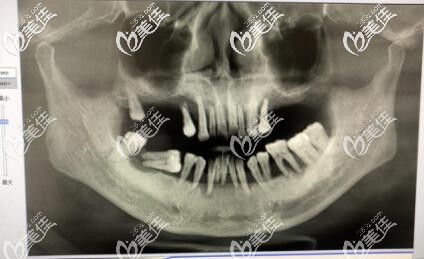

醫(yī)生介紹:李孟奇 美奧口腔昆山機構種植院長第二屆奧齒泰AIC種植病例分享會白銀獎德國BEGO全口種植認證醫(yī)師瑞典Nobel全口種植認證醫(yī)師擅長項目全口即刻種植ALL-ON-4/6,美學種植,微創(chuàng)種植,各類骨增量手術,種植并發(fā)癥處理,疑難牙齒拔除,各類牙列缺損修復,牙周膜齦手術,各類口腔疑難修復的診治。醫(yī)生簡介李孟奇,美...